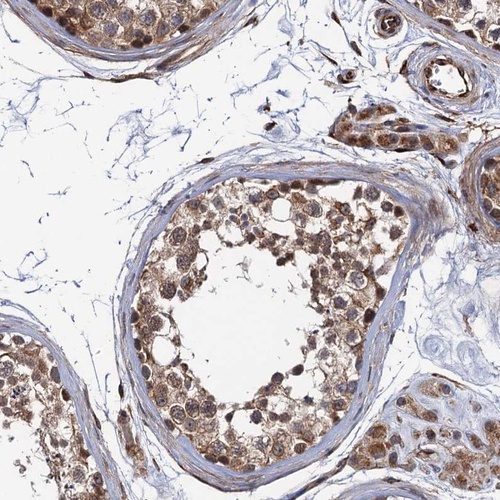

Immunohistochemical staining of human testis shows moderate cytoplasmic positivity in cells in seminiferous ducts.